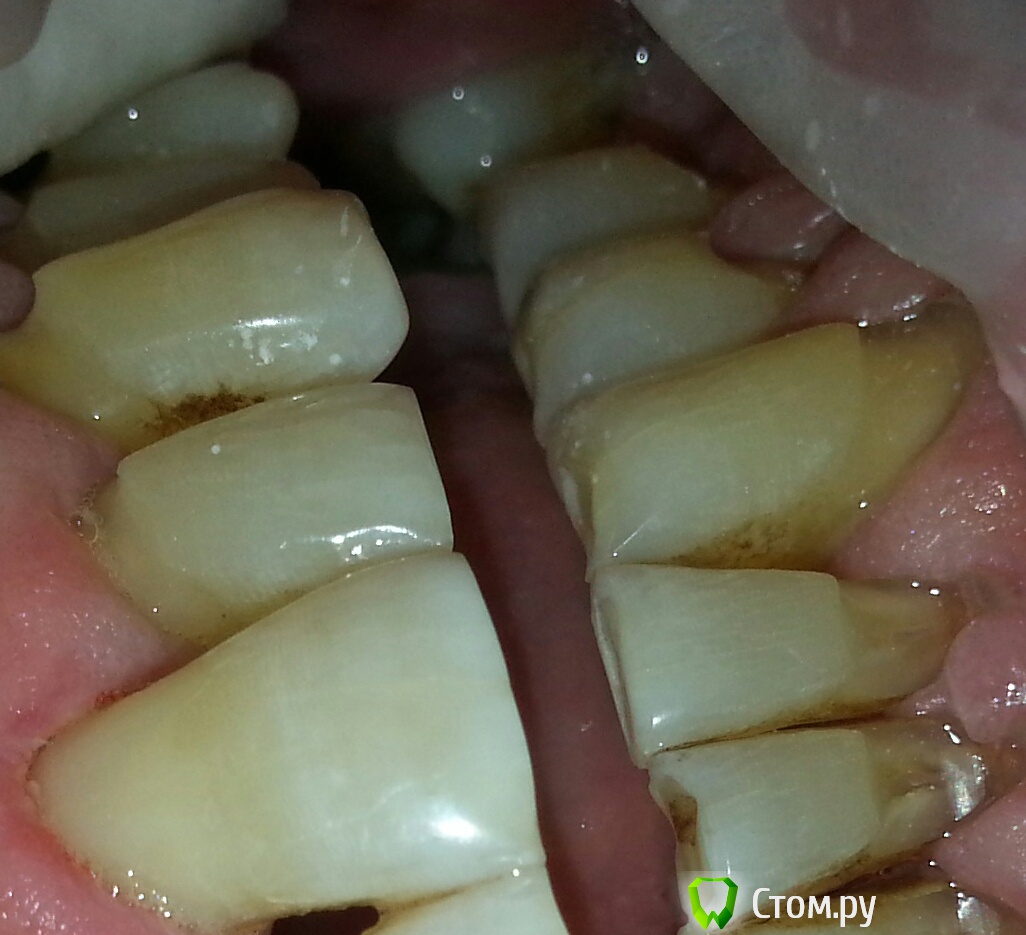

Антонина Николаевна Опубликовано 26 февраля, 2014 Поделиться Опубликовано 26 февраля, 2014 Сплошные клиновидные дефекты((((( пациенту 55 лет Ссылка на комментарий

Антонина Николаевна Опубликовано 26 февраля, 2014 Поделиться Опубликовано 26 февраля, 2014 21 запломбировала Еnamel hri plus Ссылка на комментарий

Гарриевич Опубликовано 26 февраля, 2014 Поделиться Опубликовано 26 февраля, 2014 (изменено) Мне кажется что тут нужно искать другое решение, чем композитное восстановление. Если прикинуть размер коронки резца, то вы восстанавливали композитом уже выше ЦЭС Ps цвет подобрали прилично Изменено 26 февраля, 2014 пользователем Гарриевич 1 Ссылка на комментарий

Антонина Николаевна Опубликовано 27 февраля, 2014 Поделиться Опубликовано 27 февраля, 2014 я тоже понимаю что причина не устраняется одним пломбированием. Пациенту объяснила все. Пациент странно реагирует на это. Молчит. Он хочет запломбировать пару дефектов и на этом остановиться,я так поняла. Его особо не волнует ситуация во рту)))) ну а так не мешало бы и к пародонтологу на консультацию,ортопеду и т.д.Серьезно заняться ртом)))) Ссылка на комментарий